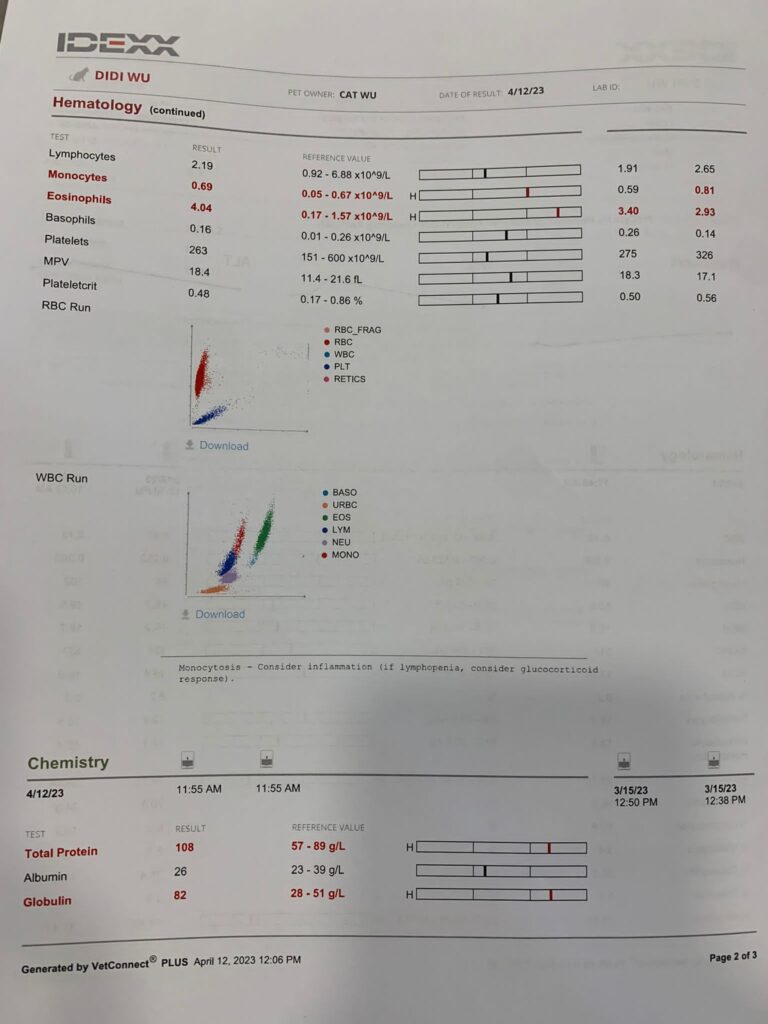

1110am: see dr d for review.

4.37kg, bladder not big. need to do urine, and

UPC. Told dr d to do alt cos his is not readable that time (manage to pop in some Sam e).

alt can read now, not good but can read 25x – will continue w Sam e.

stop ab – neu glob wbc all not much improvement. And mos Eos thingy elevated – can be due to some cancer thingy. but that will be eos 40, but didi Eos is 4+.

so non conclusive again.

UPC improve to 0.25, but still got to continue ursofalk and semintra. if weight maintain, review in 2 months. If weight drop, review in 1 month. I think didi mouth is the cause of the inflammation leh. but no way I’ll let him do dental.

Still can feel the enlarge spleen and liver enlarge too – so retake Chem 10

Cos dr d needs alt glob

Cbc also, end up take wellness package

Remaining teeth maybe 3-4, not good.

Clip nails

Heart lung sound ok

1253pm: still waiting for bloods and results

HCT 29.2%, Erm drop leh. (Semintra loh) – but have to continue (UPC 0.43) and Clav have to continue

Sdma 13 back to normal

Alt can’t read for 2 times – his liver Erm must check again.

Review on 10/17 apr latest (total 6-8 weeks of Clav)